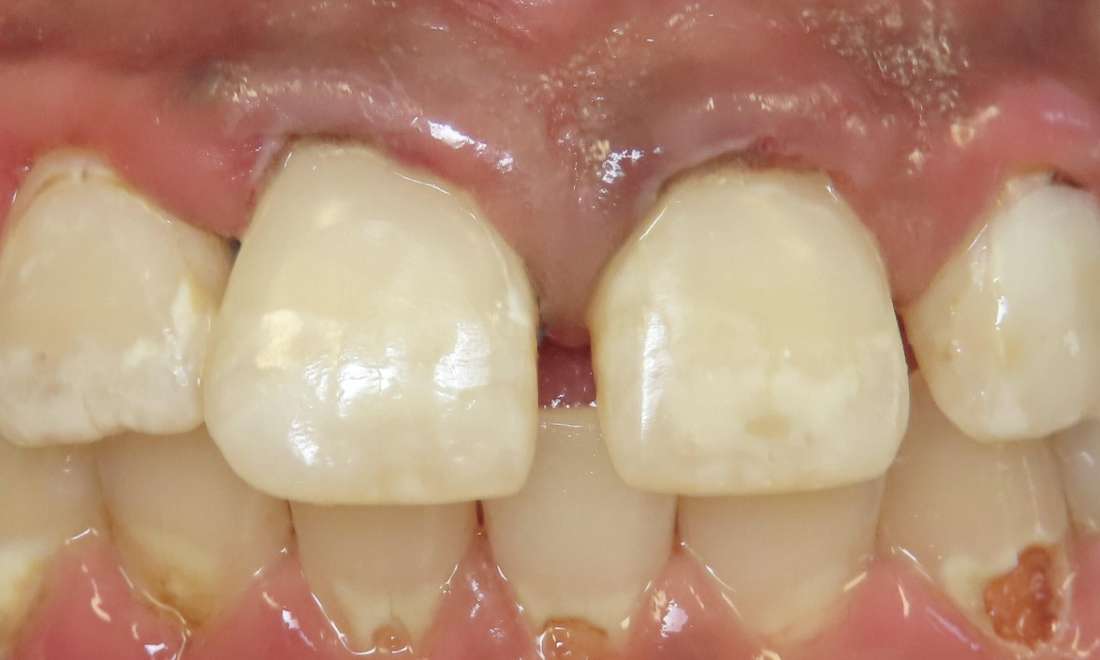

Transforming chipped, uneven, or discolored front teeth has never been easier with anterior composite bonding. This patient had very unsightly cavities on both front teeth. Within about an hour, the cavities were cleaned out and composites were placed. She was so happy with the result. This quick, minimally invasive procedure can give your smile a natural, refreshed look in just one visit.